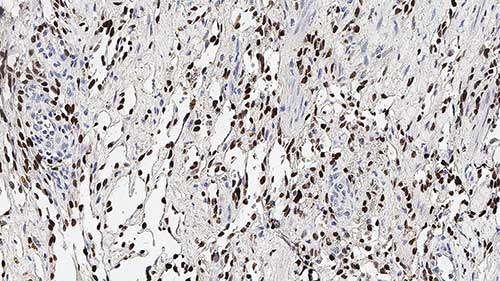

Human lymphoma: immunohistochemistry staining for CD31. Note the membrane staining of endothelial cells. CD31: Clone JC70A

CD31 antigen (PECAM-1) is a single chain transmembrane glycoprotein with a molecular weight of 130 to 140 kD. The CD31 molecule is expressed on the surface of platelets, monocytes, granulocytes, B cells and at the endothelial intracellular junction. The molecule has an extracellular domain that contains six Ig-like homology units of C2 subclass, typical of cell-to-cell adhesion molecules. This domain mediates endothelial cell-to-cell adhesion, plays a role in endothelial contact and may serve to stabilize the endothelial cell monolayer. The CD31 molecule also has a cytoplasmic domain with potential sites for phosphorylation after cellular activation. The properties of CD31 antigen suggest that it is involved in interactive events during angiogenesis, thrombosis, and wound healing. Angiogenesis is essential for tumor growth and metastases.